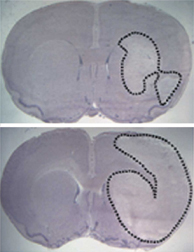

BRAIN SHIELD. A rat with extra neuroglobin in its brain (top) suffers less tissue damage (outlined areas) after a stroke than a typical rat (bottom) does. Y. Sun et al./PNAS